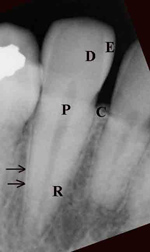

A thorough knowledge of tooth anatomy is important for proper diagnosis of dental disease and for recognition of dental apparatus. Each tooth contains distinct layers visible on conventional radiographs (figure: tooth anatomy). The anatomic crown is the portion of the tooth that is covered by enamel. Enamel, formed from ameloblasts, is the most dense tissue in the human body, composed of 97% inorganic salts. Enamel appears as the most radiopaque layer of the tooth on conventional radiographs.

The layer deep to the enamel, dentin, is a calcified, porous tissue, the second most dense tissue in the body. Dentin, laid down by odontoblasts, is a comprised of 65% inorganic salts, and forms the bulk of the tooth. Dentine is less dense than enamel, and appears as a gray opacity on conventional radiographs (figure: tooth anatomy). Dentin surrounds the pulp chamber, which lies deep within the anatomical crown, and the pulp, or root canals within the root of the tooth. Pulp consists of connective tissue, nerves, lymph channels, and blood vessels and is visualized as a radiolucency generally in the center of the anatomical crown and root extending to the apex. Reserve odontoblasts embedded within the lacunae of the dentin lay down secondary, or reparative dentin and reduce the pulp cavity and root canal size with age.

In an individual with either advanced, chronic, or refractive periodontal disease alveolar bone may be completely lost leaving only the residual basal bone. The wall of the alveolar socket, or lamina dura, is made of dense cortical bone. It appears on a radiograph as a white line next to the dark line of the periodontal ligament space. The periodontal ligament space, containing the periodontal ligament, is visualized between the lamina dura and the tooth root as a radiolucent line.

The periodontal ligament is comprised of radiolucent collagen bundles and functions to stabilize the teeth within their sockets. Its appearance varies from tooth to tooth, depending upon the overall periodontal health. It generally has a thin radiolucent appearance from the CEJ to the root apex. Endodontic or dental pulp pathology shows as a widened radiolucency within the periapical region that may extend toward the top of the tooth but narrows as it goes superiorly. Periodontal pathology, on the other hand, shows as an ever widening radiolucency from the tooth root toward the CEJ and the top of the tooth.

| E - enamel; D - dentine; P - root pulp; R - tooth root; arrows - lamina dura |